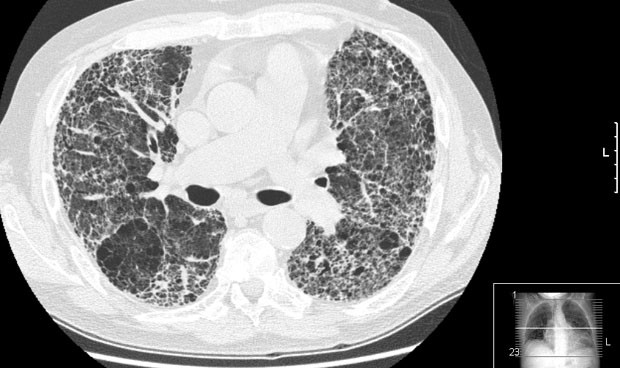

La Sociedad Española de Neumología y Cirugía Torácica (Separ) ha advertido de que la pandemia de Covid-19 ha condicionado un "retraso diagnóstico" en el último año en fibrosis pulmonar idiopática (FPI) y de linfangioleiomiomatosis (LAM), lo que conlleva peor pronóstico, tras "años trabajando para mejorar el diagnóstico rápido".

La FPI afecta a 10 personas por cada 100.000 habitantes, más a hombres que a mujeres, especialmente mayores de 60 años. Se produce por una reparación anómala del pulmón que provoca una cicatriz (fibrosis). Se llama "idiopática" porque "hasta ahora no se ha podido identificar el agente causal inductor del daño pulmonar inicial". "Aun así, en los últimos años hemos mejorado en el conocimiento de la patogenia de esta enfermedad y han aparecido tratamientos antifibróticos que antes no existían y que nos han permitido mejorar la expectativa de vida de estos pacientes", explica María Molina, neumóloga y directora del PII-EPID (acrónimo de Programa Integral de Investigación de las EPID), de Separ.